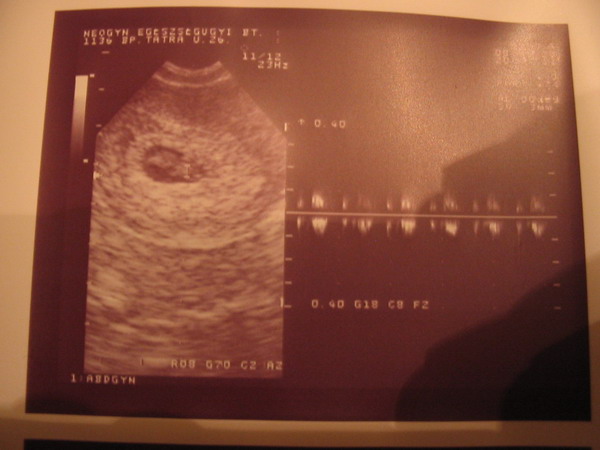

Óóóóóó Istenem! Ez a fotó gyönyörű!!!! Látszik a kis pocaklakód!

Menten elbőgöm magam!

Hát igazi Csipkerózsika történeted van. Tényleg hinni kell a csodákban, mert te vagy az egyik élő példa. Nem semmi, hogy ennyi beavatkozás meg herce-hurca után spontán sikerül. Tényleg nem véletlenül mondják, hogy amikor nem számítasz rá, akkor sikerül.Nagyon örülünk neked!